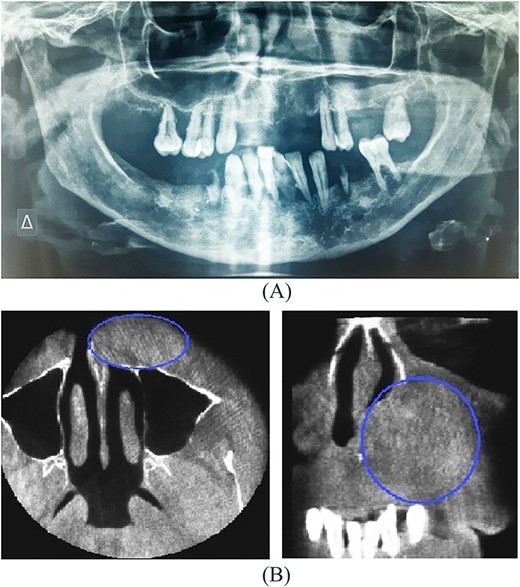

A 54-year-old-Caucasian female was referred to our department with a swelling of the left maxillary area (Fig. 1), actively inflaming. Antibiotics were prescribed, and after a week, the swelling persisted but was painless, roundish, fluctuant in palpation, sizing ~3 cm in diameter. The overlying mucosa was normal and mobile over the lesion. Clinical examination also revealed an extraoral asymmetry over the nasolabial sulcus because of the presence of this lesion causing obstruction of the left nostril. The patient presented with poor oral hygiene and the orthopantomogram revealed periodontal disease (Fig. 2a). CBCT imaging revealed a low density, ovoid, cystic soft tissue mass of 3.4 × 2.3 × 3 cm in close contact with the alar base. The maxilla near the lesion appeared concave, because of the cyst’s pressure, but without erosion (Fig. 2b). The patient was advised to undergo a contrast-enhanced computed tomography (CT) scan, but she did not wish to perform any other imaging study. The patient’s medical history was non-contributory.

Imaging includes an orthopantomogram to exclude other odontogenic lesions, and CT imaging to estimate the exact dimensions and the extension of the cyst to the neighboring structures of the nose. Imaging typically records a homogeneous, non-contrast enhancing cystic lesion anterior to the piriform opening. Remodeling of the underlying maxillary bone may be seen in larger cysts as well. Both present cases demonstrated in imaging well-defined cystic lesions in deep lateral nasal areas. On MRI, these cysts can appear as homogeneous intermediate intensity T1 signals and homogeneous high-intensity T2 signals. However, CT imaging is the preferred option in the pre-operative diagnosis of nasolabial cysts [11].